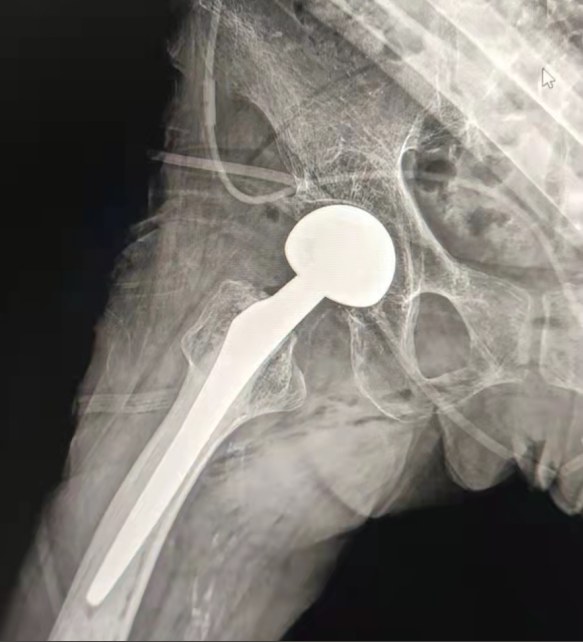

Caso compartido | Un paciente de 70 años de edad, recibió el reemplazo total de cadera con sistema de cadera cementado Lepu

Sistema cementado de la cadera:

Materiales de aleación de Co-Cr-Mo

Alta resistencia al desgaste

Gran fuerza mecánica

Diseño de hilo de hombro

Fácil de instalar, mantener y ajustar el ángulo

Tratamiento superficial pulido

Para lograr un excelente crecimiento óseo Asegurando la estabilidad de la fijación temprana

12/14 Diseño cónico estándar

Proximal Mix Anatomy

Design Collection Europe and USA Stem Características

Tratamiento distal del corte de Adge de ambos lados

Reducir la presión en la cavidad medular